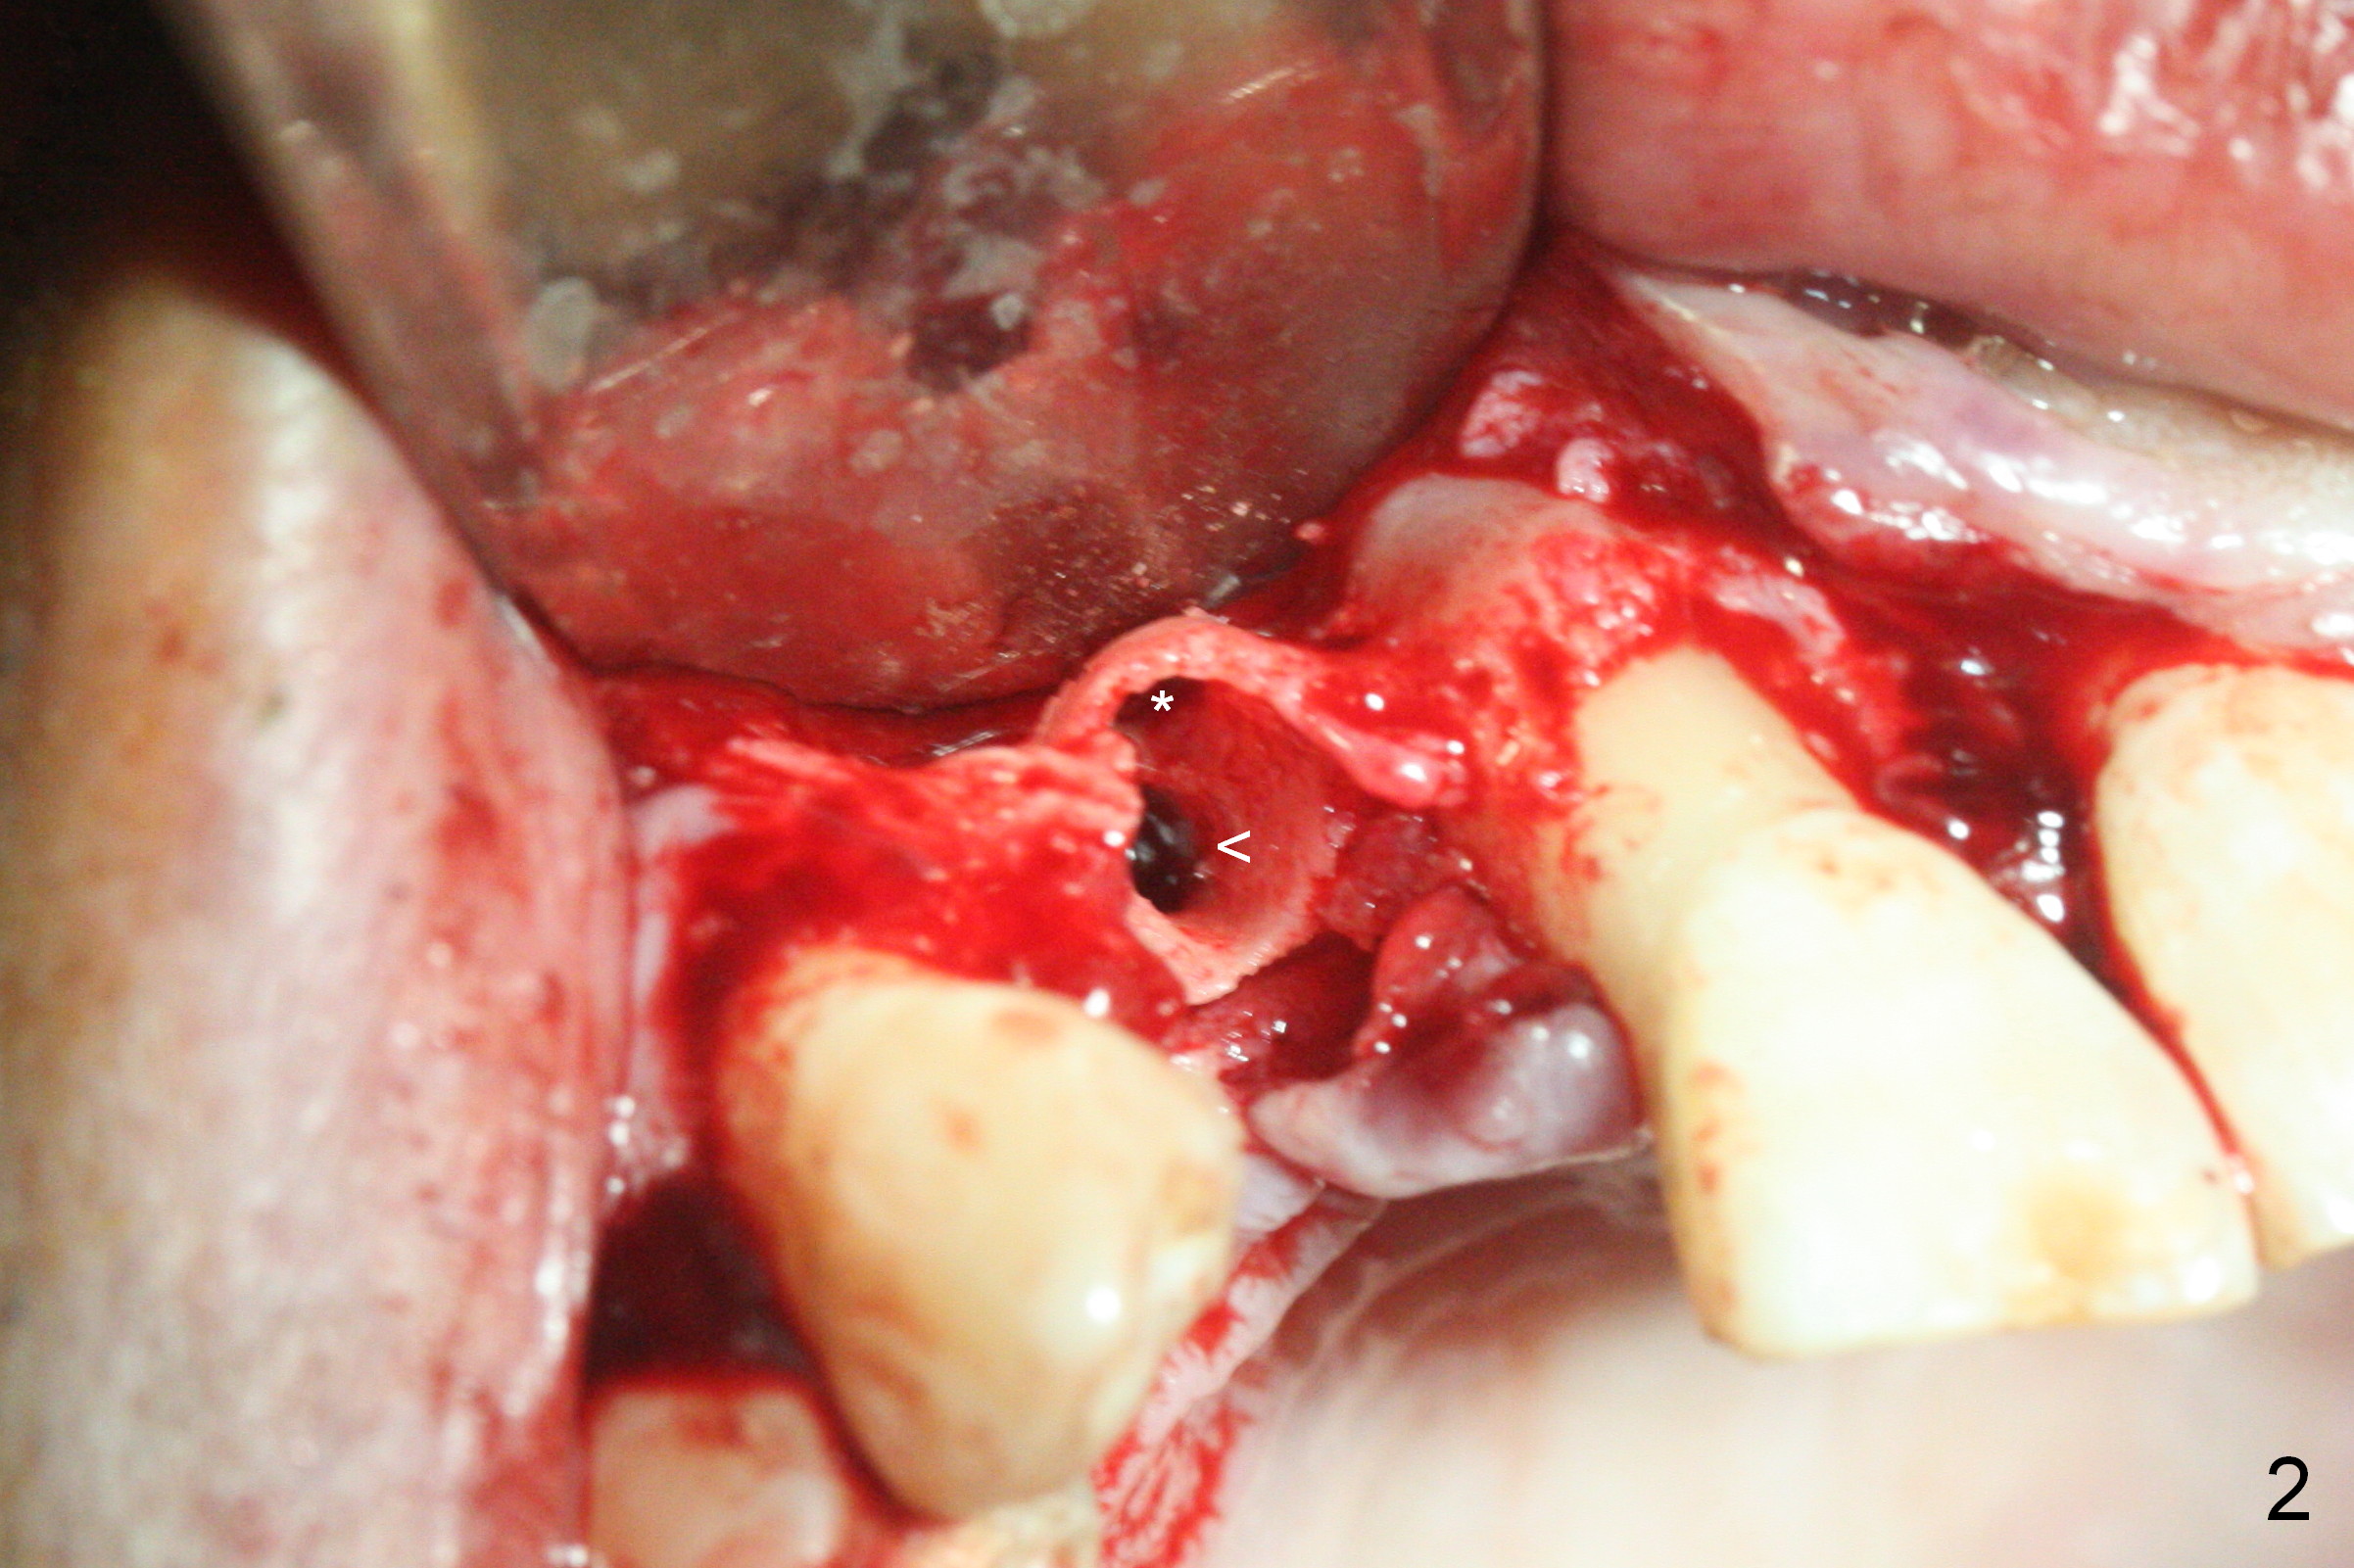

When the flaps are raised, the buccal plate is found to be perforated (Fig.2 *); osteotomy is being established in the narrow palatal wall (<). When a 3x17 mm (tissue-level) 15 ° 1-piece implant is placed (Fig.3,5 P), the incisal end of the implant is between the incisal edge of the central incisors and that of the tooth #10 (Fig.6) so that the temporary crown (Fig.7 T) is slightly buccal with sufficient palatal clearance with the opposing dentition.